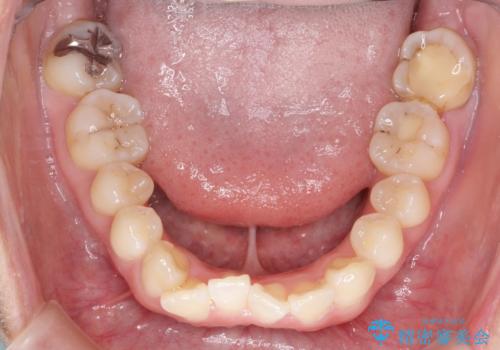

【インビザライン】前歯の凸凹をなおしたい

- 前歯の凸凹をなおしたいことを主訴にインビザラインにて矯正治療を行いました。

患者様にしっかりとインビザラインを使用して頂けたことで綺麗な仕上がりとなりました。